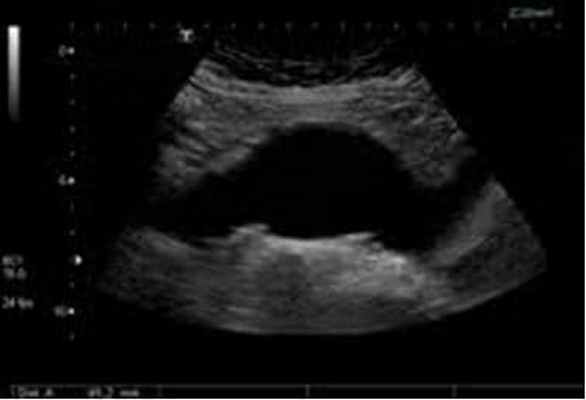

Ультразвуковое дуплексное исследование – "золотой стандарт" скринингового обследования пациентов (обнаружение и динамическое наблюдение);

Аневризма брюшной аорты - это локальное или диффузное расширение диаметра брюшного отдела аорты более 3 см. Истончение стенки и развитие аневризмы аорты в основном носит приобретенный характер и обусловлено атеросклерозом в 95% случаев, на остальные причины (неспецифический аортоартериит, туберкулезное, сифилитическое, ревматическое поражение аорты) приходится всего 5%.

КТ-ангиография - "золотой стандарт" предоперационного обследования и в тех случаях, когда информации при УЗДС недостаточно;